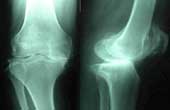

| 減慢腰及膝蓋關節退化 | |

| 年齡的增長,加上日積月累的操勞工作,退化的問題就像呼吸一樣來....... |